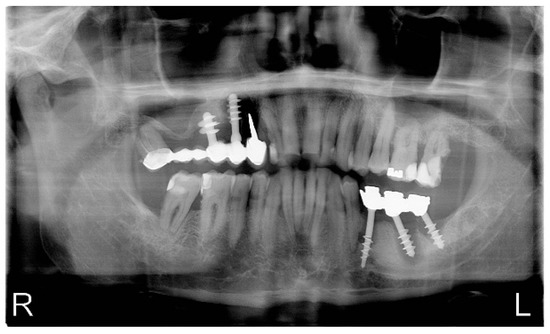

Pilot Study of Use of Nitric Oxide in Monitoring Multiple Dental Foci in Oral Cavity—A Case Report

by Magdalena Wyszyńska, Przemysław Rosak, Aleksandra Czelakowska, Ewa Białożyt-Bujak, Jacek Kasperski, Maciej Łopaciński, Nour Al Khatib and Małgorzata Skucha-Nowak

Healthcare 2022, 10(2), 195; https://doi.org/10.3390/healthcare10020195 - 20 Jan 2022

Background: The most common cause of implant loss and deteriorating restoration aesthetics is infection and chronic inflammation of the tissues around the implants. Inflammation in the oral cavity, confirmed by clinical and histopathological examination and determination of exhaled nitric oxide, is a situation [...] Read more.

Background: The most common cause of implant loss and deteriorating restoration aesthetics is infection and chronic inflammation of the tissues around the implants. Inflammation in the oral cavity, confirmed by clinical and histopathological examination and determination of exhaled nitric oxide, is a situation which may cause the complications on the whole human body. Elimination of the patology in the oral cavity in some cases is the only resonable treatment. The aims and objectives of our work is to present a gradual treatment of advanced infalmmation and present huge reduction stamp of inflammation measured with marker nitric oxide (NO) in exhaled air. Materials and Methods: Simple treatment containing elimantion of pathology in the oral cavity was conducted. Patient that came to the dental practice suffered from the inflammation caused by lack of proper hygiene. First aid in this situation was to eliminate the inflammation which may affect negatively for general health. At first visit full hygienization was performed, at the second visit roots of abutment teeth and implants were removed under local anesthesia along with cystic changes. Results: The hygiene precedures and extraction of the unsteady inflammationprosthetic restorations significantly decreased the level of NO in exhaled air. Conclusions: During the examination of the patient coming to the dental practice great attention should be paid to the coexistence of pathologies related to the oral cavity. Omission of a dental examination and possible elimination of odontogenic foci may affect the implication of the results of general diagnostics and subsequent treatment. Measuring the level of NO on exhaled air seems to be useful diagnostic method. Full article